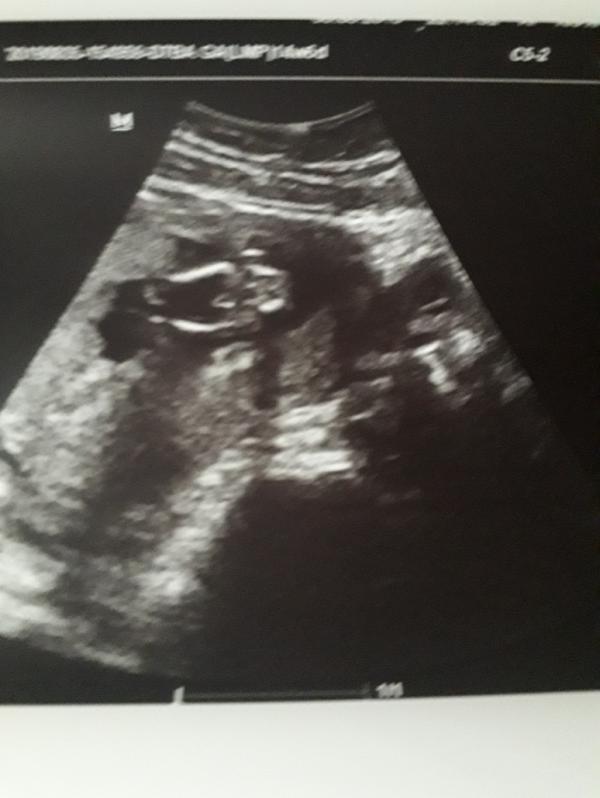

Ну,что?!Сходила я на вне очередное УЗИ,у нас буд4т второй сынишка❤Я рада!Гланое,чтоб здоровый был!А я теперь старшему сыну могу спокойно сообщить,что у него будет братик)))